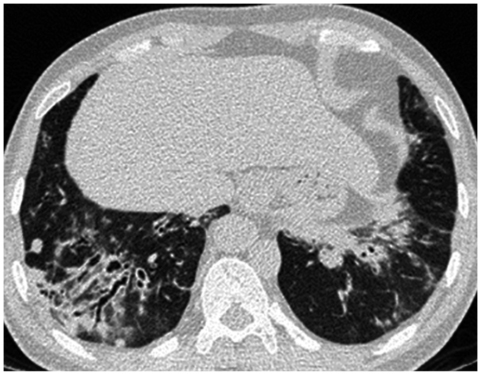

【随访】

患者明确诊断后院外口服药物治疗,咳嗽、咳痰、气急症状较前好转,2018年4月26日复查肺功能提示DLCO/pre 65.2%,较前相仿;动脉血气分析提示SaO2 95.8%,较前好转;胸部CT平扫:病灶较前有所吸收(图7)。

图7胸部CT平扫示双肺下叶基底段病灶较前明显吸收